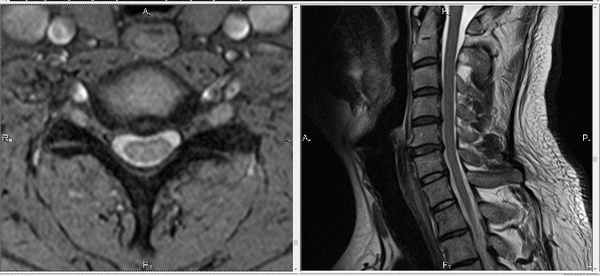

Небольшого размера грыжа шейного отдела позвоночника:

Такого размера грыжи могут протекать бессимптомно.

На МРТ снимке, который ниже, видны не только нижнешейный отдел позвоночника, но и грудной. Удачное сочетание, поскольку шейно-грудной переход нередко бывает причиной боли:

При длительных и упорных болевых проявлениях со стороны позвоночника, кроме МРТ шеи иногда приходится делать и МРТ исследование грудного отдела. Это нужно для дифференциальной диагностики. Пример — метастатическое поражение грудного отдела могут давать боли и в шее:

: